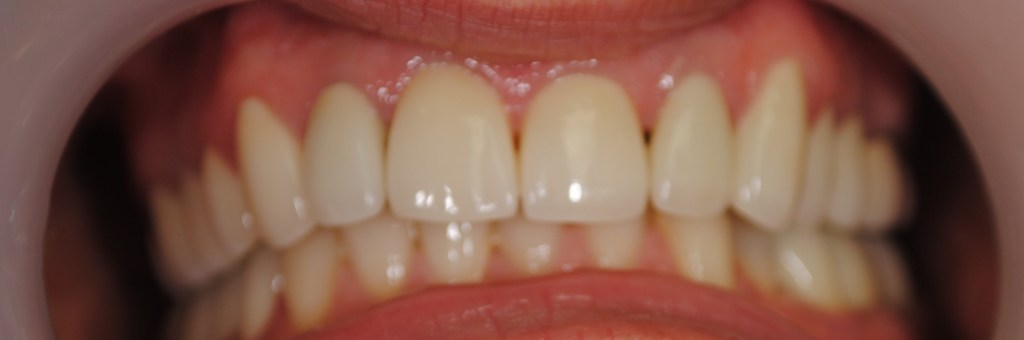

Kozmetikai és funkcionális kezelés: felső torlódott fogak kiegyenesítése, koronák enyhe kifele döntése, mélyharapás korrigálása.

A választott korona típusa: CAD/CAM (komputer vezérelt tervezés/megmunkálás) technológiával készült cirkónium (fémmentes) szóló koronák.

A választott fogszín: A2

A protetikai munka elkészülésének ideje: 5 munkanap.